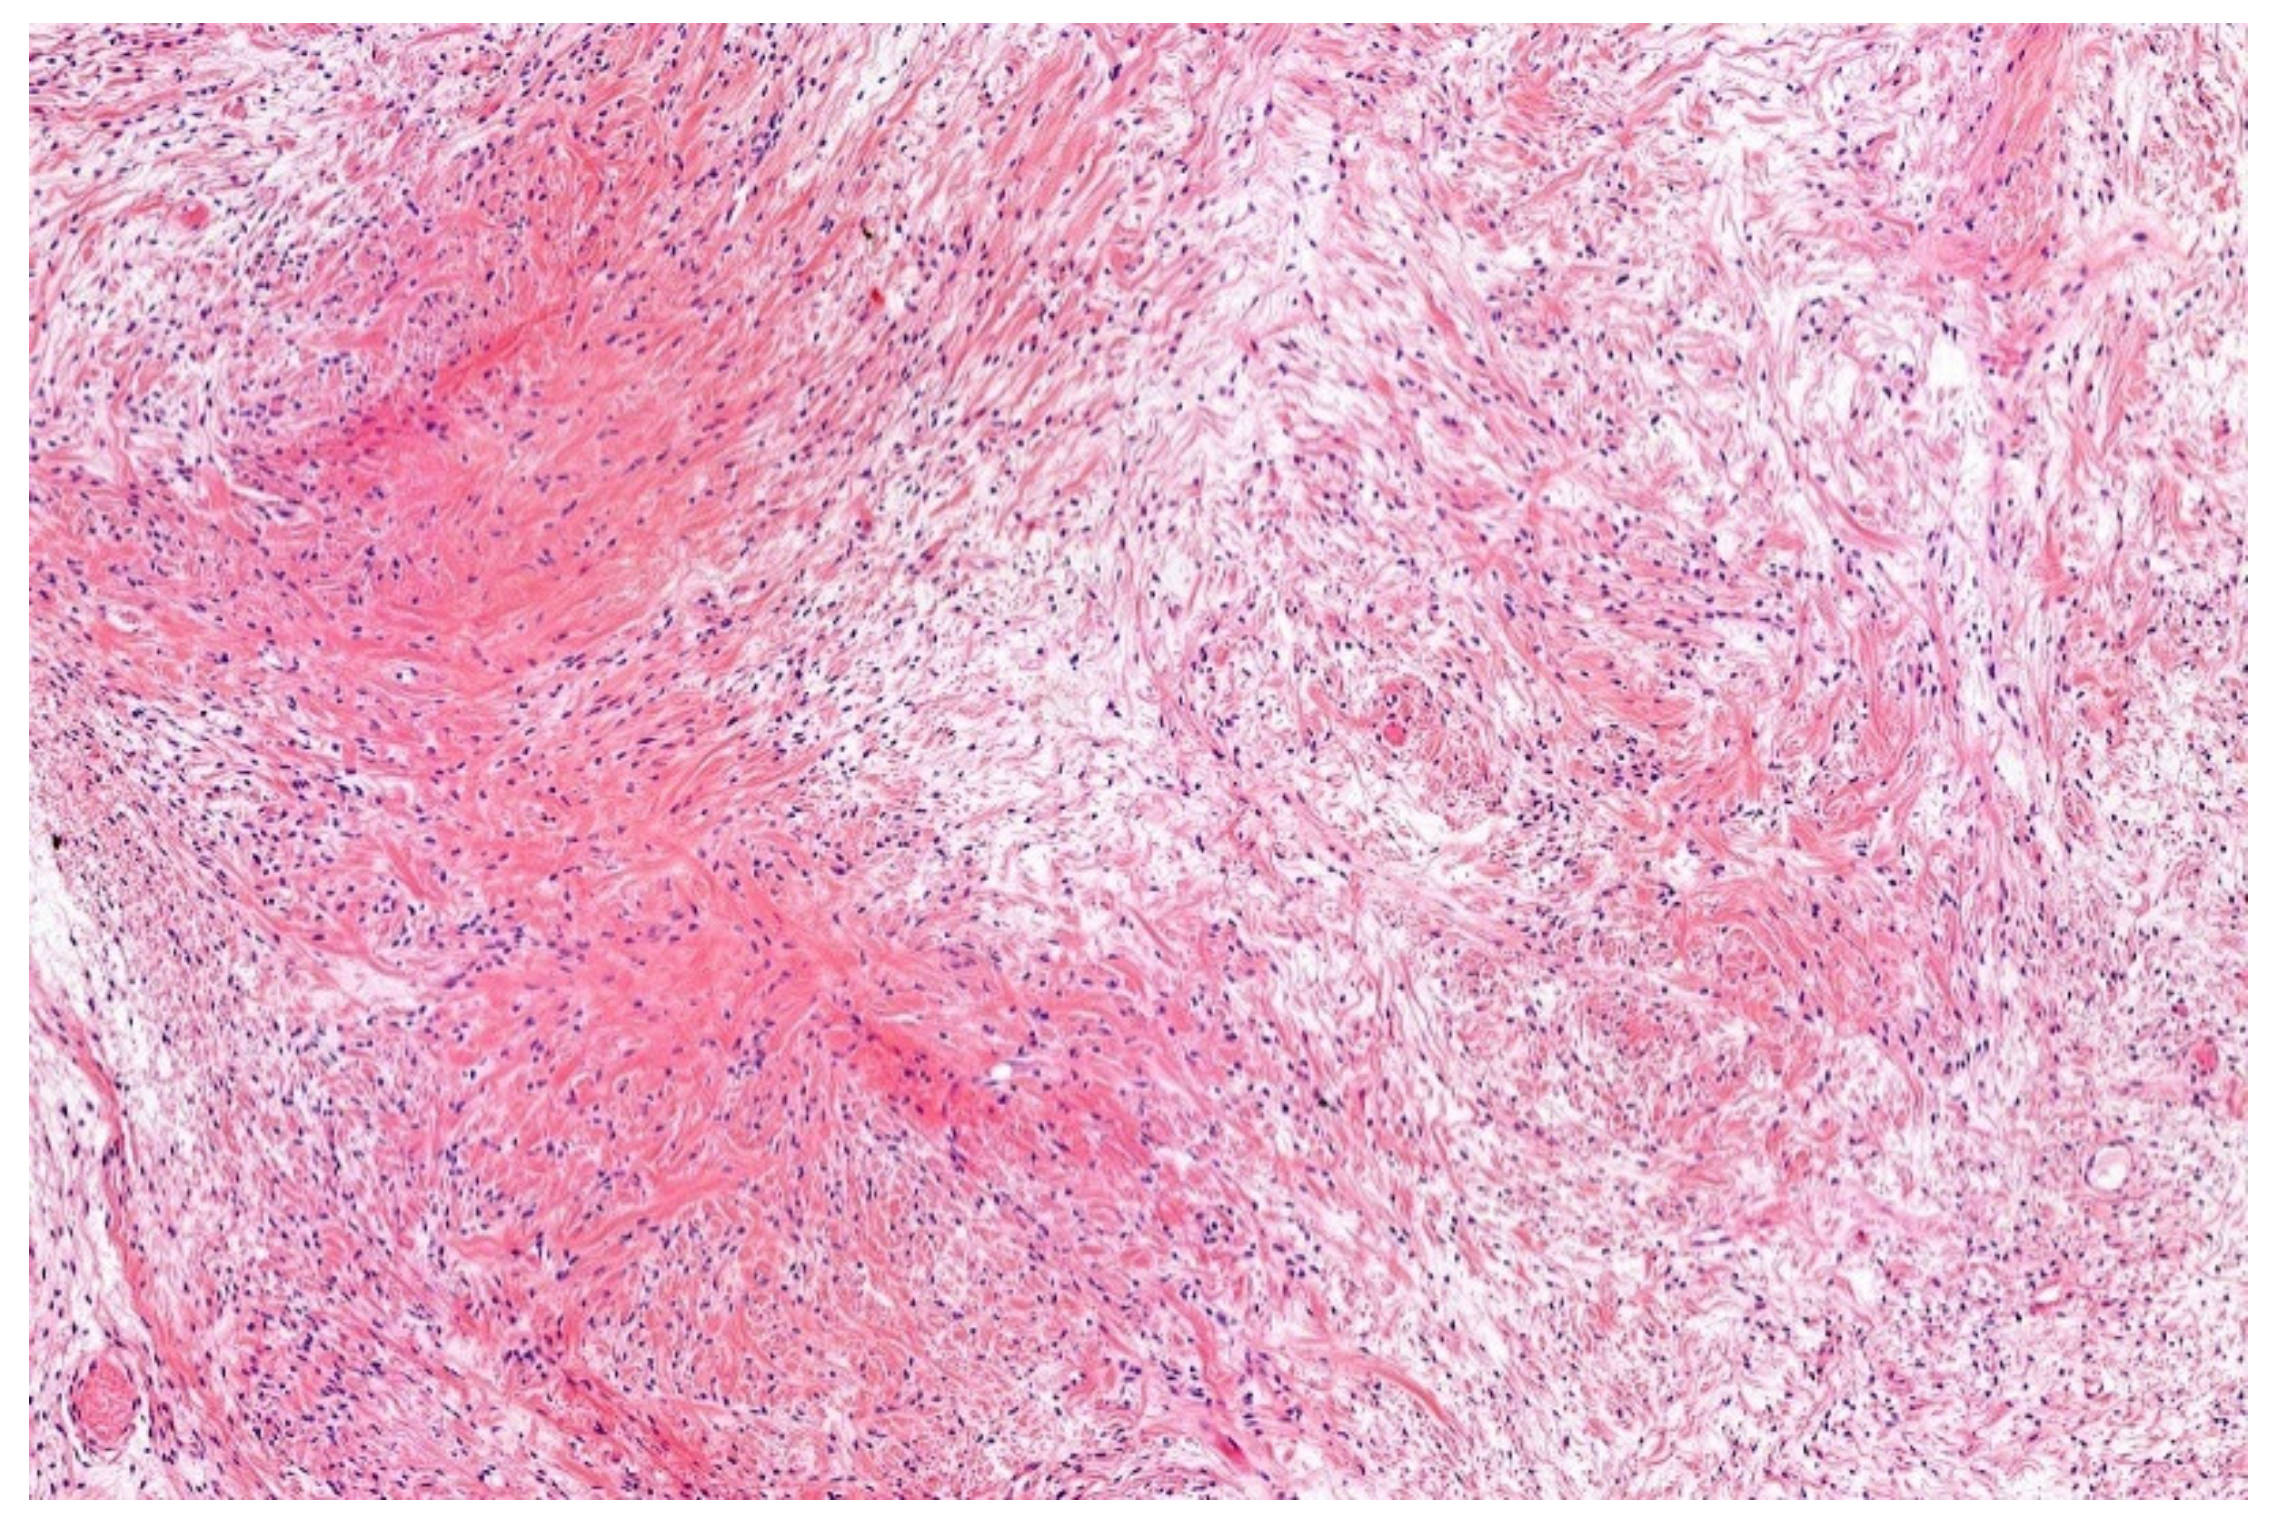

7. Low-Grade Fibromyxoid Sarcoma (LGFMS)/Sclerosing Epithelioid Fibrosarcoma (SEF)

- Guillou, L.; Benhattar, J.; Gengler, C.; Gallagher, G.; Ranchère-Vince, D.; Collin, F.; Terrier, P.; Terrier-Lacombe, M.J.; Leroux, A.; Marquès, B.; et al. Translocation-positive low-grade fibromyxoid sarcoma: Clinicopathologic and molecular analysis of a series expanding the morphologic spectrum and suggesting potential relationship to sclerosing epithelioid fibrosarcoma: A study from the French Sarcoma Group. Am. J. Surg. Pathol. 2007, 31, 1387–1402. [Google Scholar] [CrossRef] [PubMed]

- Evans, H.L. Low-grade fibromyxoid sarcoma. A report of two metastasizing neoplasms having a deceptively benign appearance. Am. J. Clin. Pathol. 1987, 88, 615–619. [Google Scholar] [CrossRef] [PubMed]

- Evans, H.L. Low-grade fibromyxoid sarcoma: A clinicopathologic study of 33 cases with long-term follow-up. Am. J. Surg. Pathol. 2011, 35, 1450–1462. [Google Scholar] [CrossRef] [PubMed]

- Evans, H.L. Low-grade fibromyxoid sarcoma. A report of 12 cases. Am. J. Surg. Pathol. 1993, 17, 595–600. [Google Scholar] [CrossRef]